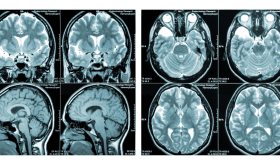

Esclerosis Múltiple - Infografía

Aprende más sobre esta patología con esta infografía o en www.medicinaysaludpublica.com